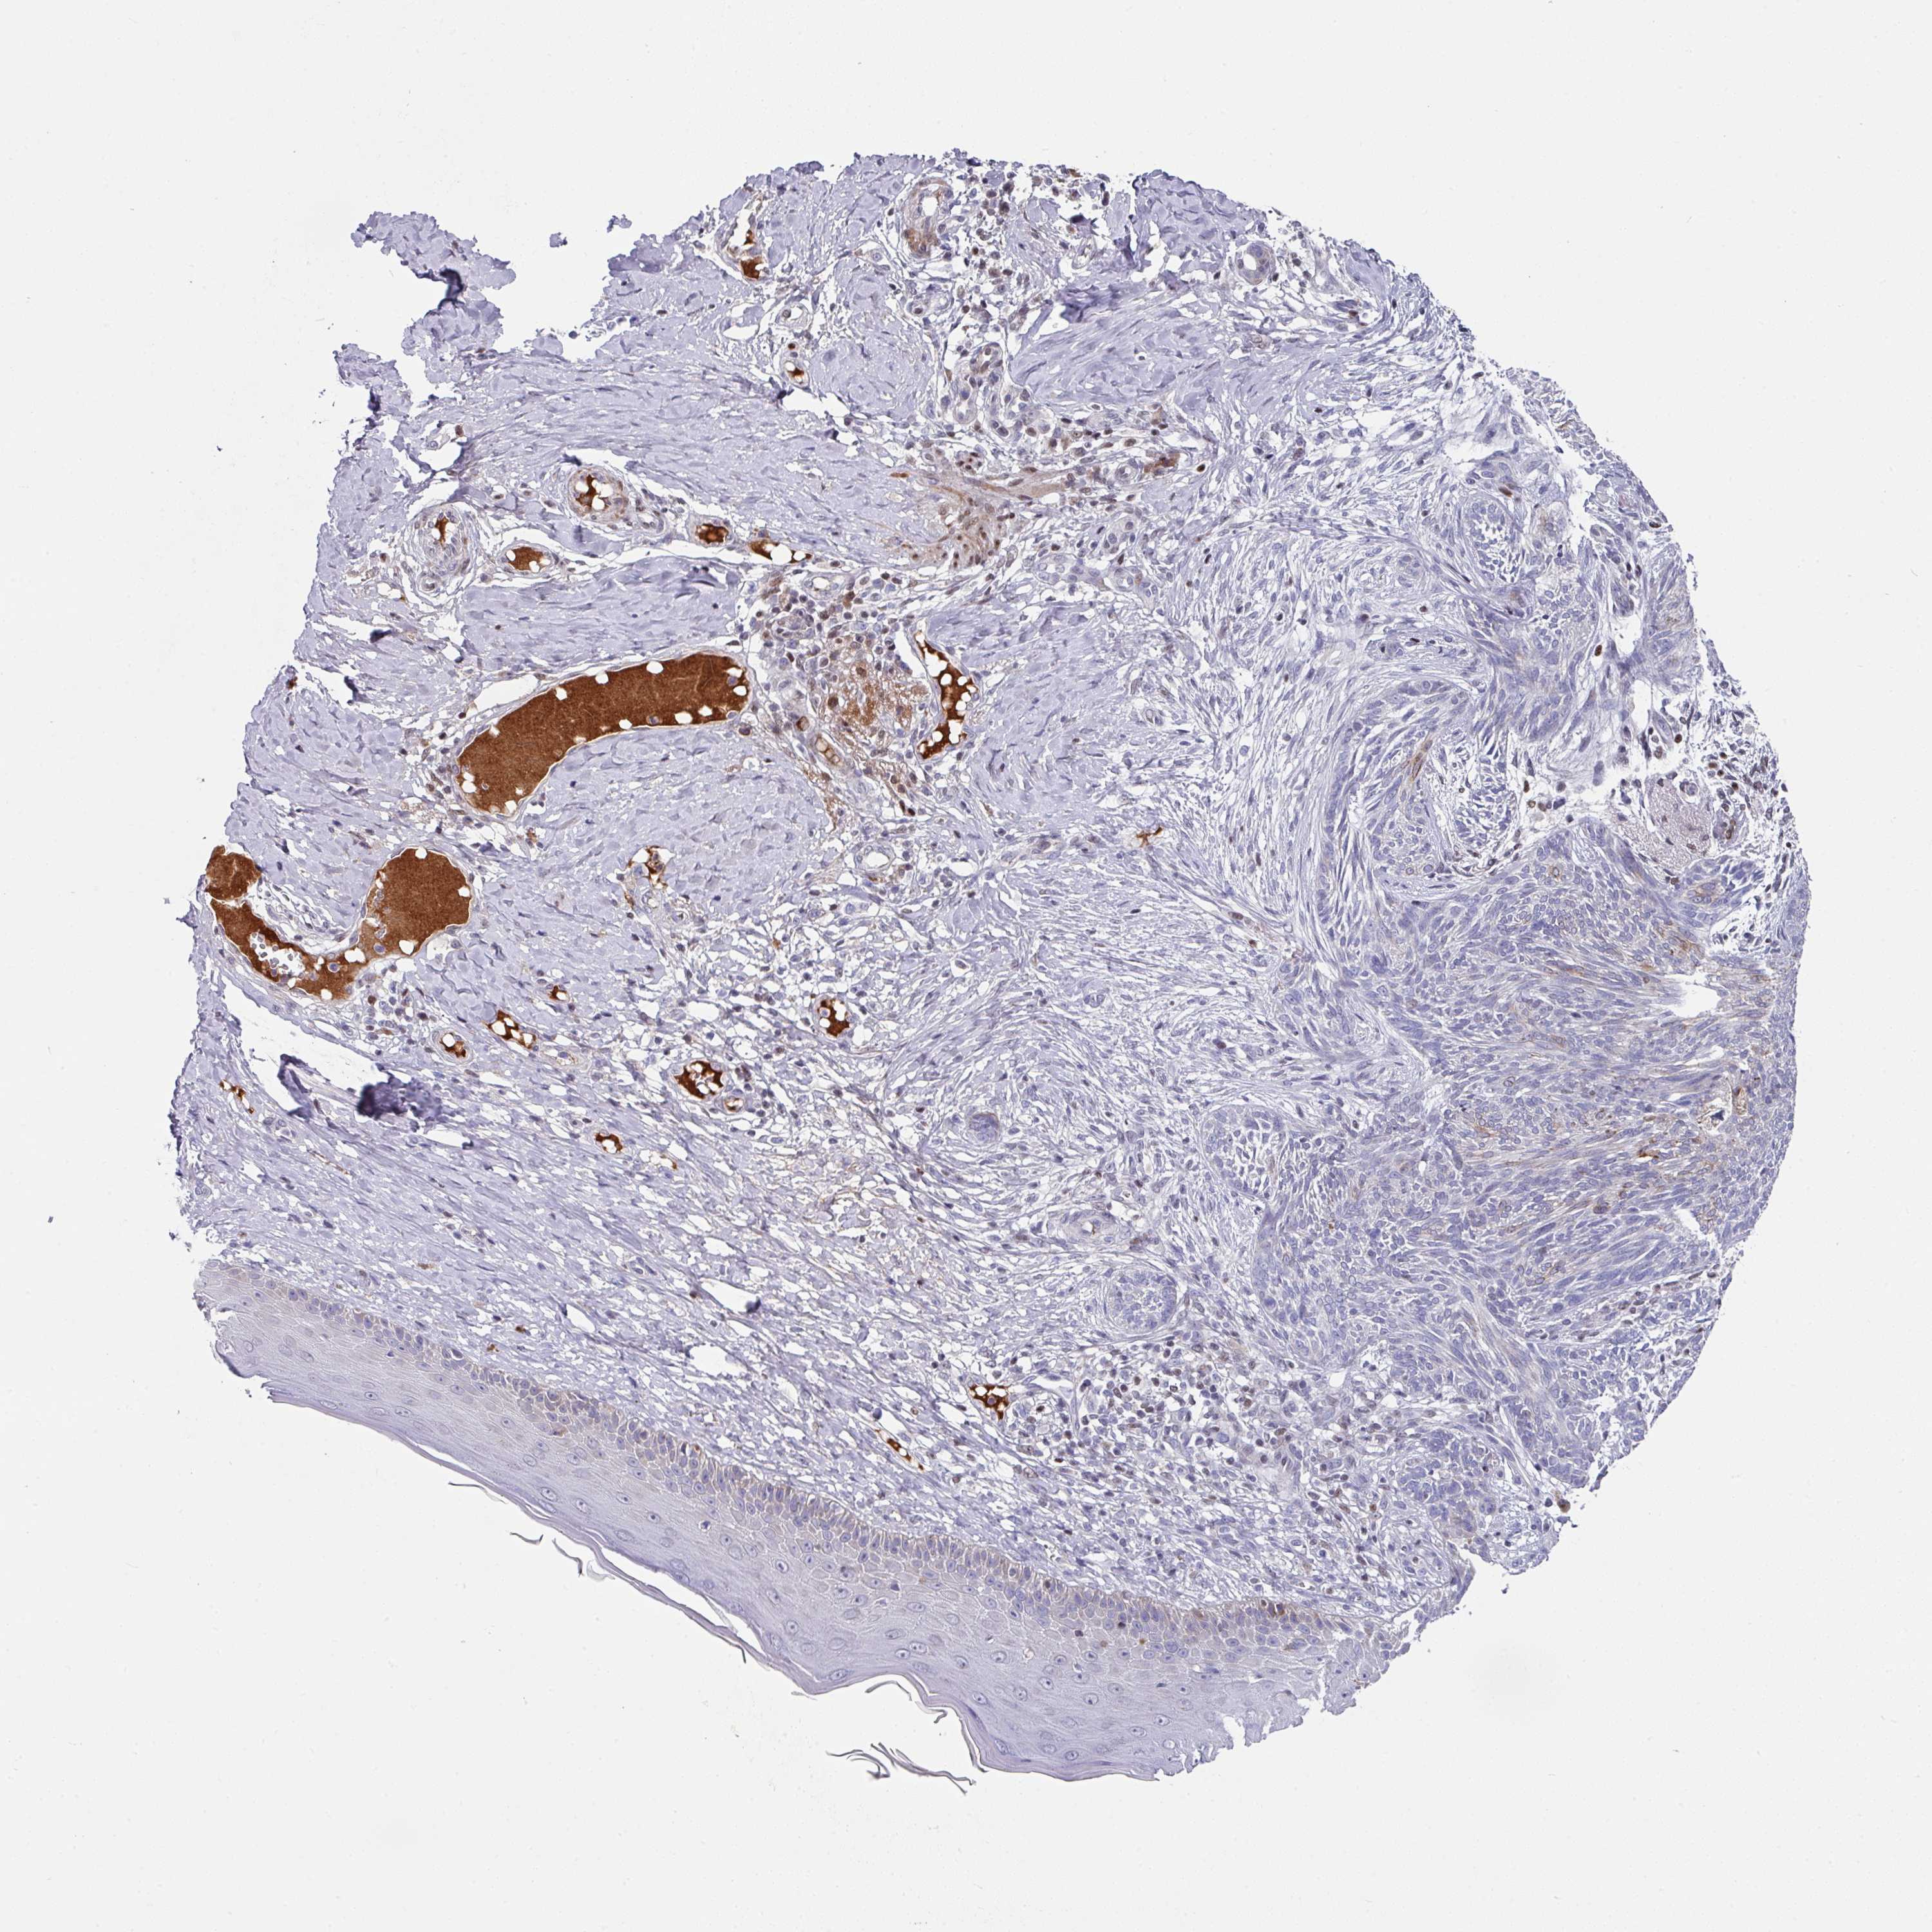

SKIN CANCER - Protein expressioni

A mouse-over function shows sample information and annotation data. Click on an image to view it in a full screen mode. Samples can be filtered based on level of antibody staining by selecting one or several of the following categories: high, medium, low and not detected. The assay and annotation is described here.

Each image is clickable and will lead to virtual microscopy that enables deeper exploration of all samples and also displays staining intensity scores, fraction scores and subcellular localization as well as patient and tissue information for each sample.

Antibody HPA056480

Squamous cell carcinoma, NOS